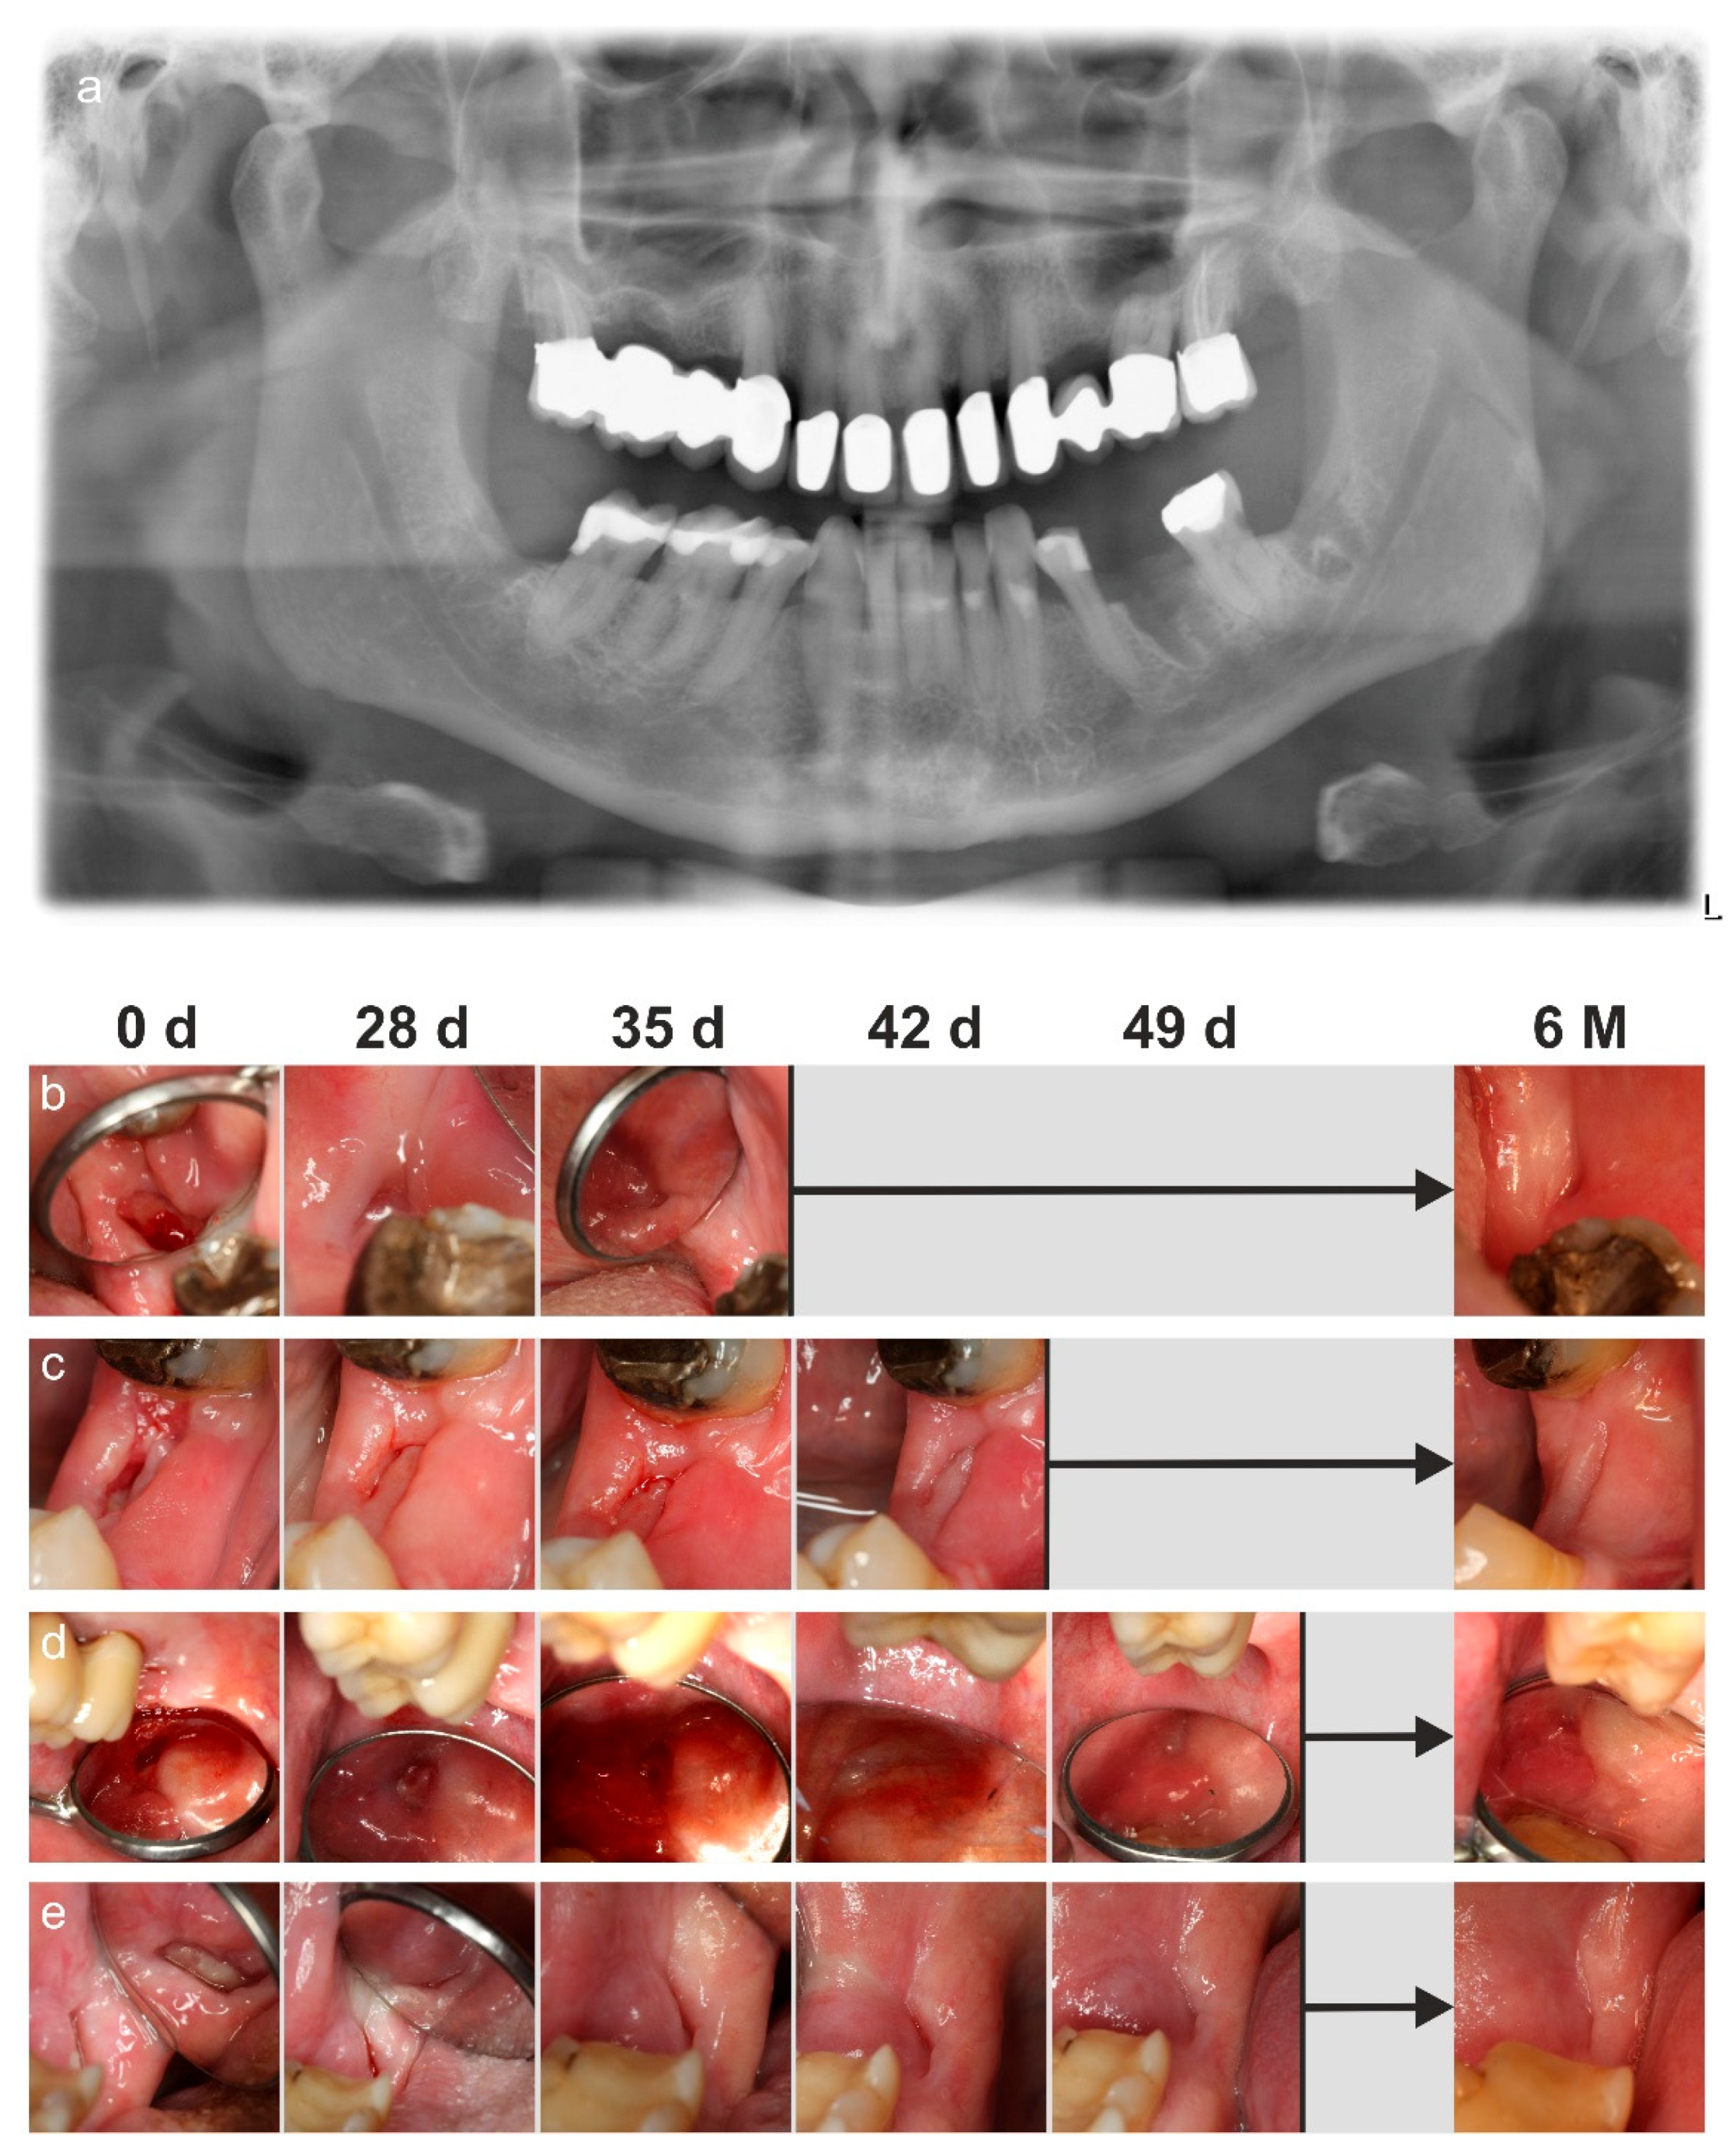

2. Case Report